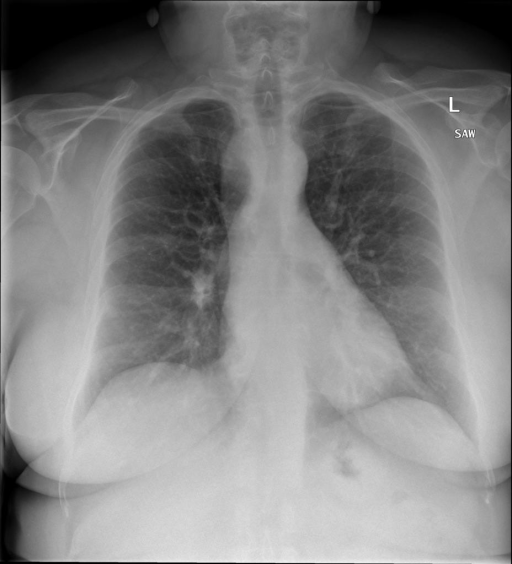

## 本文贡献  - 借助ChatGPT以及公开的数据集,我们构造了一个`X光影像-诊断报告`对的医学多模态数据集; - 我们将构建的中文胸部X光片诊断数据集在[VisualGLM-6B](https://github.com/THUDM/VisualGLM-6B)进行微调训练,并开放了部分训练权重用于学术研究; ## 数据集 - [MIMIC-CXR](https://physionet.org/content/mimic-cxr-jpg/2.0.0/)是一个公开可用的胸部X光片数据集,包括377,110张图像和227,827个相关报告。 - [OpenI](https://openi.nlm.nih.gov/faq#collection)是一个来自印第安纳大学医院的胸部X光片数据集,包括6,459张图像和3,955个报告。 在上述工作中,报告信息都为非结构化的,不利于科学研究。为了生成合理的医学报告,我们对两个数据集进行了预处理,并最终得到了可以用于训练的**英文报告**。除此之外,为了更好的支持中文社区发展,借助ChatGPT的能力,我们将英文报告进行了中文翻译,并最终形成了可用于训练的数据集。 |数据集|数量|下载链接| |:-|:-|:-| |MIMIC-CXR-zh|-|-| |OpenI-zh|6,423|[诊疗报告(英文)](./data/openi-en.json)、[诊疗报告(中文)](./data/Xray/openi-zh.json) 、[X光影像](https://pan.baidu.com/s/13GBsDMKf6xBZBSHpoWH_EA?pwd=k9sh)| ## 快速上手 ### 1.安装环境 ```bash # 安装依赖 pip install -r requirements.txt # 国内换源安装依赖 pip install -i https://mirrors.aliyun.com/pypi/simple/ -r requirements.txt ``` 此时默认会安装`deepspeed`库(支持`sat`库训练),此库对于模型推理并非必要,同时部分`Windows`环境安装此库时会遇到问题。 如果想绕过`deepspeed`安装,我们可以将命令改为: ```bash # 安装依赖 pip install -i https://mirrors.aliyun.com/pypi/simple/ -r requirements_wo_ds.txt # 安装SwissArmyTransformer pip install -i https://mirrors.aliyun.com/pypi/simple/ --no-deps "SwissArmyTransformer>=0.3.6" ``` ### 2.模型推理 |模型权重|下载链接| |:-|:-| |checkpoints-XrayGLM-300|-| |checkpoints-XrayGLM-3000|-| CLI推理: ```python python cli_demo.py --from_pretrained checkpoints/checkpoints-XrayGLM-3000 --prompt_zh '详细描述这张胸部X光片的诊断结果' ``` 更多[参数](https://github.com/WangRongsheng/XrayGLM/blob/main/cli_demo.py#L16) ### 3.模型训练(复现XrayGLM) > 我们所使用的硬件为:四卡A100 80GB - (1)准备[诊疗报告(中文)](./data/Xray/openi-zh.json)和[X光影像](https://pan.baidu.com/s/13GBsDMKf6xBZBSHpoWH_EA?pwd=k9sh)在`data/Xray`文件夹下; - (2)开始训练: ```bash # 设置CUDA变量,主要是为了解决有时候直接训练而出现无法正确加载到显卡问题 export CUDA_VISIBLE_DEVICES=0,1,2,3 # 开始训练 bash finetune_XrayGLM.sh ``` 这里的复现过程非常简单,主要是很多过程我们都为大家准备好了,大家可以随时复现一个自己的`XrayGLM`。 ### 4.模型训练(通用) ## 效果展示 影像诊断: |X光影像|诊疗报告(医生)|XrayGLM| |:-|:-|:-| ||根据X射线图像,心脏大小正常,肺部看起来很清晰。已经排除了肺炎、积液、水肿、气胸、腺病、结节或肿块的存在。该发现表明一切正常。换句话说,总体印象是胸部正常。|X光片显示,心脏大小正常。肺部没有气胸或胸腔积液的证据。骨骼结构看起来没有任何异常。总的来说,X光片表明没有发现急性心肺疾病的迹象。| ||X光图片显示没有扭曲的区域、可疑的骨质不透明度或胸腺积液。心脏大小轻微增大,但非常稳定。此外,没有气胸的证据,肺野也正常。总体来说,X光片显示没有急性心脏异常,但要注意轻微的心脏扩大。|X光片显示,心脏大小正常。肺部和纵隔轮廓清晰,没有气胸或胸腔积液的证据。骨骼结构完整,没有任何急性异常。| ||心影形态在正常范围内。没有急性骨质异常。有可能出现没有明显的吸水或肺实质状况的线索。没有大面积积液或气胸。有可能怀疑其有误吸或肺实质问题。为了确诊和治疗,可能需要进行适当的影像学随访。|心脏大小正常,肺部和纵隔轮廓清晰。没有急性异常或活动受限的证据。没有任何明显的气胸、胸腔积液或肺不张的迹象。此外,也没有发现任何局灶性骨质异常或其他急性疾病。| 多轮对话: |X光影像|诊疗报告(医生)| |:-|:-| ||右侧主动脉突出观察到。心脏大小正常。胸部未发现明显的肺气肿、胸膜积液或可疑的肺部病变。报告指出已知右侧主动脉情况正常。| ```bash >> X光影像路径:./data/Xray/861_1.png >> 用户:这是一张什么图? >> XrayGLM:这张图片显示的是一张肺部检查的X光片。 >> 用户:请描述这张胸部X光片的诊断结果 >> XrayGLM:心脏大小正常,肺部清晰。没有急性心肺疾病的证据。 >> 用户:是否存在肺气肿? >> XrayGLM:没有肺气肿。心脏大小正常,肺部清晰。没有发现急性心肺疾病的证据。 >> 用户:平时饮食该注意什么? >> XrayGLM:饮食应该健康,均衡。建议增加蛋白质的摄入量,因为蛋白质有助于维持肌肉和骨骼的健康。多食用蔬菜、水果、全谷物以及健康的脂肪来源如橄榄油、鱼类等可以帮助获得足够的维生素和矿物质。此外,避免过度饮酒或吸烟,这些习惯可能会对心脏健康产生负面影响。 ``` ## 未来展望 1. 模型的能力更多来源于数据的支持,`OpenI-zh`作为微调数据集,其数据量足以支持研究,在更广泛的任务和性能表现上,我们认为**在大规模数据集上预训练并在高质量少量数据集上微调是一种可行的方案**; 2. 普遍意义的理解上,视觉多模态模型=视觉模型+语言模型。除了需要关注视觉模型信息与语言模型输出的搭配外,还需要**额外关注到语言模型的加强,在人机的对话中,尤其是医疗语言模型的问答上,除了专业的医疗问题回答,带有人文情怀的有温度的回答更应该是我们追寻的目标**。 ## 项目致谢 1. [VisualGLM-6B](https://github.com/THUDM/VisualGLM-6B)为我们提供了基础的代码参考和实现; 2. [MiniGPT-4](https://github.com/Vision-CAIR/MiniGPT-4)为我们这个项目提供了研发思路; 3. ChatGPT生成了高质量的中文版X光检查报告以支持XrayGLM训练; 4. [gpt_academic](https://github.com/binary-husky/gpt_academic)为文档翻译提供了多线程加速; 5. [MedCLIP](https://github.com/RyanWangZf/MedCLIP) 、[BLIP2](https://huggingface.co/docs/transformers/main/model_doc/blip-2) 、[XrayGPT](https://github.com/mbzuai-oryx/XrayGPT) 等工作也有重大的参考意义;  这项工作由[澳门理工大学应用科学学院](https://www.mpu.edu.mo/esca/zh/index.php)硕士生[王荣胜](https://github.com/WangRongsheng) 、[段耀菲](https://github.com/IsBaSO4) 、[李俊蓉](https://github.com/lijunrong0815)完成,指导老师为檀韬副教授、[彭祥佑](http://www.patrickpang.net/)老师。 *特别鸣谢:[USTC-PhD Yongle Luo](https://github.com/kaixindelele) 提供了有3000美金的OpenAI账号,帮助我们完成大量的X光报告翻译工作 ## 免责声明 本项目相关资源仅供学术研究之用,严禁用于商业用途。使用涉及第三方代码的部分时,请严格遵循相应的开源协议。模型生成的内容受模型计算、随机性和量化精度损失等因素影响,本项目无法对其准确性作出保证。即使本项目模型输出符合医学事实,也不能被用作实际医学诊断的依据。对于模型输出的任何内容,本项目不承担任何法律责任,亦不对因使用相关资源和输出结果而可能产生的任何损失承担责任。 ## 项目引用 如果你使用了本项目的模型,数据或者代码,请声明引用: ```bash @misc{wang2023XrayGLM, title={XrayGLM: The first Chinese Medical Multimodal Model that Chest Radiographs Summarization}, author={Rongsheng Wang, Yaofei Duan, Junrong Li, Patrick Pang and Tao Tan}, year={2023}, publisher = {GitHub}, journal = {GitHub repository}, howpublished = {\url{https://github.com/WangRongsheng/XrayGLM}}, } ``` ## 使用许可 此存储库遵循[CC BY-NC-SA](https://creativecommons.org/licenses/by-nc-sa/4.0/) ,请参阅许可条款。